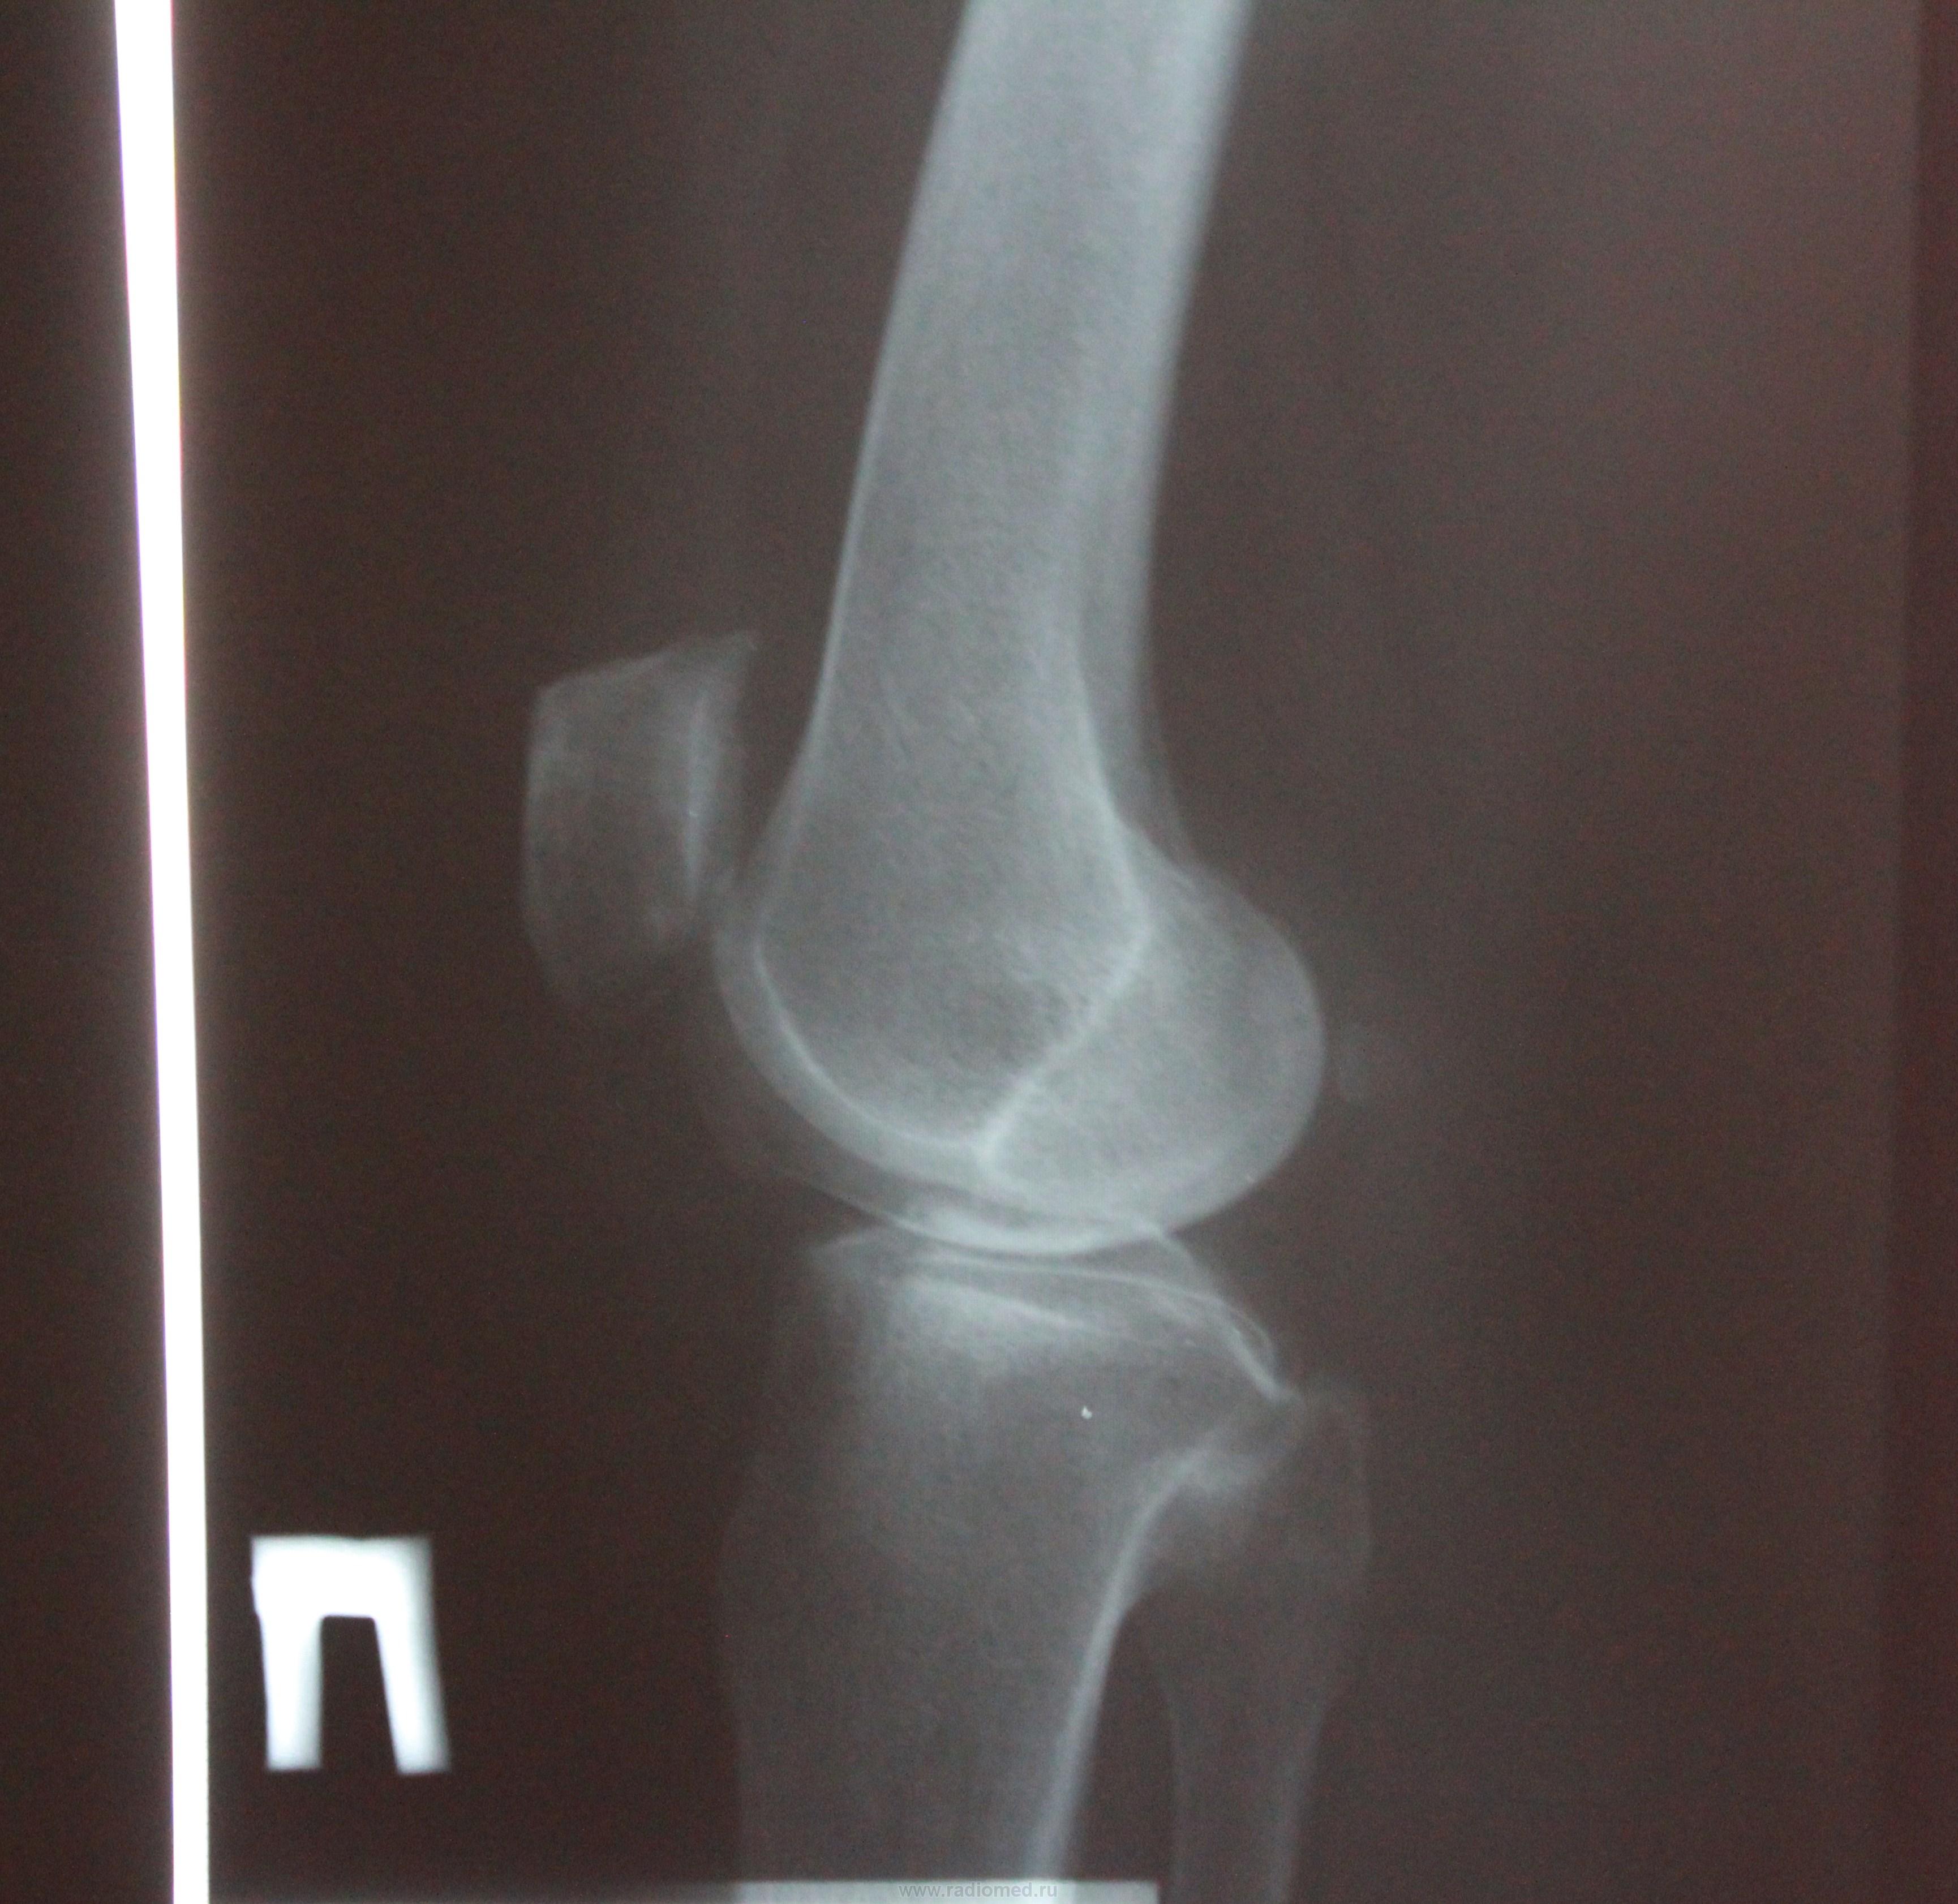

Пол пациента: Мужской пол Тип патологии: Другое Область исследования: Скелетно-мышечная система Методы исследования: Rg Гонартроз.Степень? https://radiomed.ru/sites/default/files/styles/case_slider_image/public/user/17208/img_1016.jpg?itok=h8mkxSs_ ID:24101 Ср, 31/10/2012 - 16:13 #1 фади 79 Не на сайте Был на сайте: 9 лет 2 недели назад Зарегистрирован: 30.10.2012 - 21:15 Публикации: 50 2 Ср, 31/10/2012 - 16:25 #2 Катенёв Валенти... Не на сайте Был на сайте: 7 лет 5 месяцев назад Зарегистрирован: 22.03.2008 - 22:15 Публикации: 54876 фади 79 wrote: 2 Что означает цифра "2"? Ср, 31/10/2012 - 16:50 #3 фади 79 Не на сайте Был на сайте: 9 лет 2 недели назад Зарегистрирован: 30.10.2012 - 21:15 Публикации: 50 второй степень Ср, 31/10/2012 - 17:00 #4 Катенёв Валенти... Не на сайте Был на сайте: 7 лет 5 месяцев назад Зарегистрирован: 22.03.2008 - 22:15 Публикации: 54876 фади 79 wrote: второй степень Второй степени нет, есть второя стадия по классификации Н.С. Косинской. Ср, 31/10/2012 - 17:02 #5 Катенёв Валенти... Не на сайте Был на сайте: 7 лет 5 месяцев назад Зарегистрирован: 22.03.2008 - 22:15 Публикации: 54876 Тут, даже при желании, больше первой нарыть не возможно с учетом таких краеугольных признаков, как субхондральный склероз и краевое остеофитообразование. Ср, 31/10/2012 - 17:04 #6 фади 79 Не на сайте Был на сайте: 9 лет 2 недели назад Зарегистрирован: 30.10.2012 - 21:15 Публикации: 50 А перый , второй? Ср, 31/10/2012 - 20:35 #7 maker4ik Не на сайте Был на сайте: 8 лет 11 месяцев назад Зарегистрирован: 19.10.2011 - 17:49 Публикации: 2682 1-2 Ср, 31/10/2012 - 20:51 #8 Катенёв Валенти... Не на сайте Был на сайте: 7 лет 5 месяцев назад Зарегистрирован: 22.03.2008 - 22:15 Публикации: 54876 Интересно, а почему маячит вторая? Чт, 01/11/2012 - 20:55 #9 maker4ik Не на сайте Был на сайте: 8 лет 11 месяцев назад Зарегистрирован: 19.10.2011 - 17:49 Публикации: 2682 Катенёв Валентин Львович wrote: Интересно, а почему маячит вторая? Щель медиально узковата, в верхнем полюсе надколенника (у нас принято и его учитывать) - остеофит огромный. Но на полноценную 2 все это не тянет. Чт, 01/11/2012 - 21:21 #10 Катенёв Валенти... Не на сайте Был на сайте: 7 лет 5 месяцев назад Зарегистрирован: 22.03.2008 - 22:15 Публикации: 54876 maker4ik wrote: Щель медиально узковата, в верхнем полюсе надколенника (у нас принято и его учитывать) - остеофит огромный. Но на полноценную 2 все это не тянет. Для второй сужение должно быть более 50% Чт, 01/11/2012 - 22:05 #11 алкс Не на сайте Был на сайте: 10 лет 5 месяцев назад Зарегистрирован: 24.10.2012 - 22:55 Публикации: 2915 Катенёв Валентин Львович wrote: maker4ik wrote: Щель медиально узковата, в верхнем полюсе надколенника (у нас принято и его учитывать) - остеофит огромный. Но на полноценную 2 все это не тянет. Для второй сужение должно быть более 50% А если остеофит в малоберцовой? Т.е. учитываете пожалуйста то, что относится к суставу см. пост Катенёв В.Л. Чт, 01/11/2012 - 23:19 #12 Катенёв Валенти... Не на сайте Был на сайте: 7 лет 5 месяцев назад Зарегистрирован: 22.03.2008 - 22:15 Публикации: 54876 Обработанные снимки.Приложения:

Тут, даже при желании, больше первой нарыть не возможно с учетом таких краеугольных признаков, как субхондральный склероз и краевое остеофитообразование.

Щель медиально узковата, в верхнем полюсе надколенника (у нас принято и его учитывать) - остеофит огромный. Но на полноценную 2 все это не тянет.

Для второй сужение должно быть более 50%

Обработанные снимки.